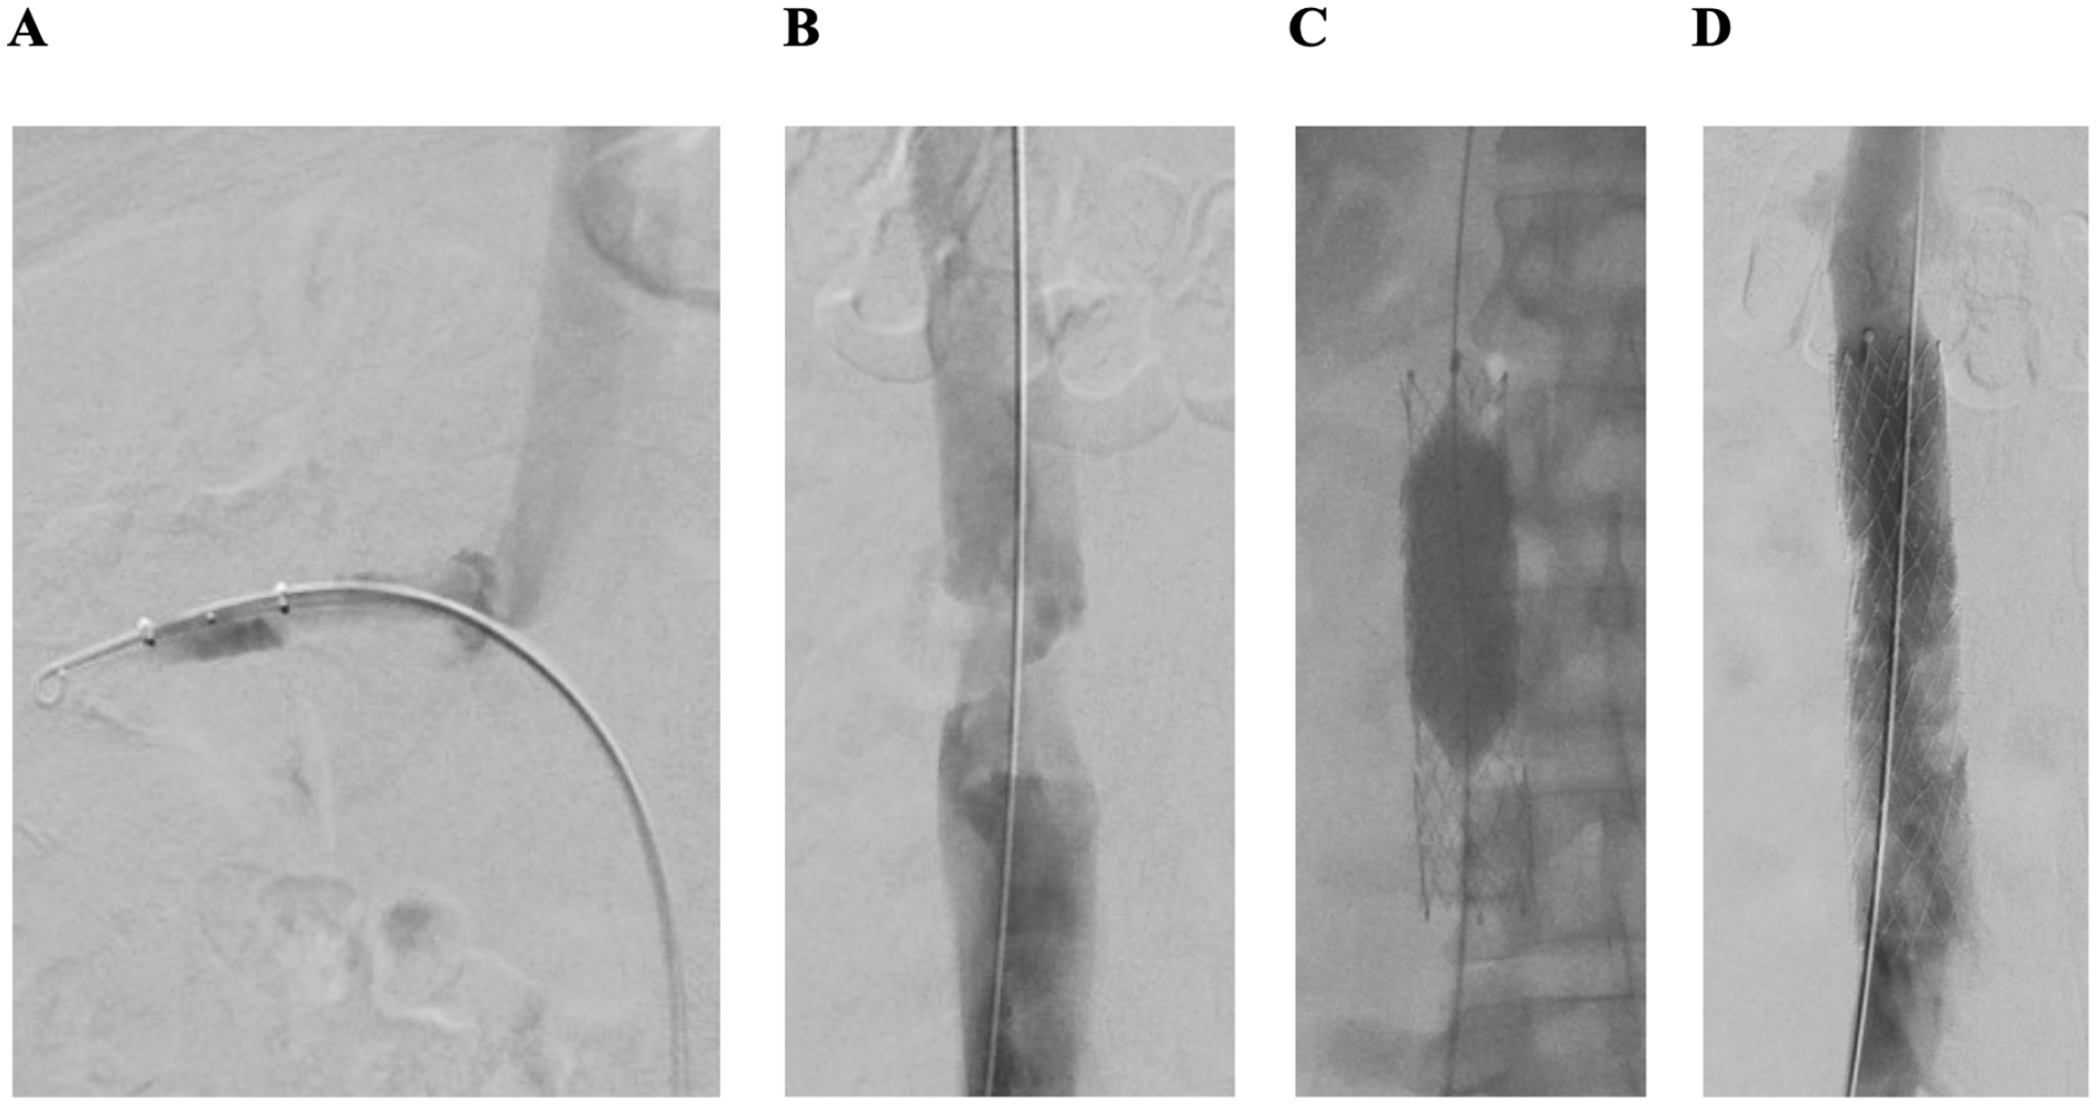

As both iliofemoral venous segments were free of thrombus, the right common femoral was punctured and a mechanical thrombectomy of both renal veins and of the infrahepatic inferior vena cava was performed using Angiojet ZelanteDVT catheter (Boston Scientific, Figure 4A). For thrombectomy of the infrarenal inferior vena cava, the Angiojet ZelanteDVT catheter (Boston Scientific) was used. A subsequent IVUS revealed a residual venous obstruction of the infrarenal inferior vena cava, which subsequently was treated by balloon angioplasty with a non-compliant 20/40 mm balloon (Atlas Gold, BARD/BD) and implantation of a 20/100 mm self-expandable venous stent (Abre, Medtronic, Figure 4B and C).

Mechanical thrombectomy of the re-occluded right renal vein and the inferior vena cava: (A) thrombectomy with Angiojet ZelanteDVT catheter (Boston Scientific) of right renal vein, (B) thrombotic stenosis of inferior vena cava, (C) postdilation after stent placement in the inferior vena cava (Abre stent 20/100 mm, Medtronic) with a non-compliant high-pressure balloon implantation (Atlas Gold 20/40 mm, BARD/BD), and (D) control phlebography of inferior vena cava after stent implantation.

Postinterventional phlebography confirmed a venous drainage of both renal veins and a satisfying flow of the inferior vena cava. Duplex ultrasound confirmed regular venous flow modulation of the inferior vena cava and of both renal veins.